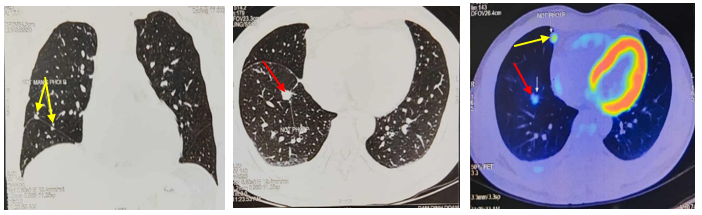

Bệnh nhân được chụp PET/CT tại Bệnh viện Vinmec cho kết quả: Các nốt đặc rải rác thùy giữa và dưới phổi phải, các nốt lớn tăng chuyển hoá FDG (suvmax 3,6), ít dịch màng phổi dày 9mm, nhiều nốt rải rác màng phổi thành ngực, hạch nhóm 2R,4R/7 rốn phổi phải, hạch lớn KT 17x10mm.

Hình 3: Hình ảnh chụp PET/CT các nốt tổn thương u tại phổi phải (mũi tên đỏ), nốt di căn màng phổi phải (mũi tên vàng)

Hình 4: Hình ảnh chụp PET/CT: Hạch trung thất, dịch màng phổi phải (mũi tên chỉ)